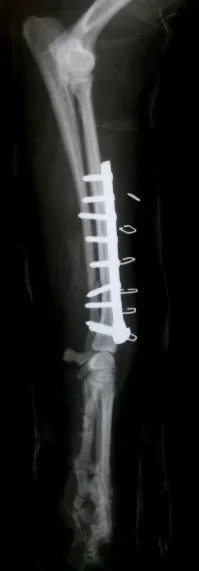

Galería de casos clínicos

Casos clínicos de cirugía (tejidos blandos, traumatología, neurocirugía, artroscopia)